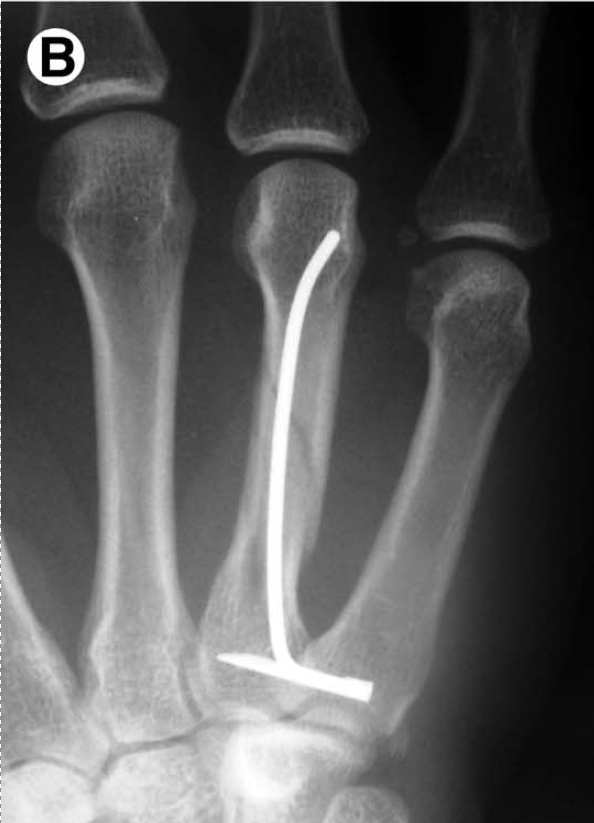

Metacarpal shaft fractures are common but consensus on the best mode of treatment has not been established. Open reduction and internal fixation with plates or screws has been performed for severely displaced fractures. Unfortunately, extensor tendon adhesions and/or unsightly scars frequently follow this form of treatment. Percutaneous flexible intramedulary nailing of metacarpal fractures provides an alternative method that minimizes these problems. The technique is simple and provides the ability to lock the nails to control length and rotation. The nails are inserted using a manually operated slotted awl and usually in an anterograde direction to prevent soft tissue irritation around the metacarpophalangeal joints. This method utilizes flexible nails (1.5 and 1.0 mm.) and closed fluoroscopically assisted reduction. Rotationally unstable or fractures with a tendency to shorten can be locked proximally using a captured transverse pin which effectively controls length and rotation. Metacarpophalangeal flexion block splinting can be used postoperatively and the nails are routinely removed after fracture healing. Experience with this technique has been favorable as it avoids exposure of the fracture, dissection around the extensor mechanism, and scar problems. It has provided excellent functional results and has presented a low complication rate.